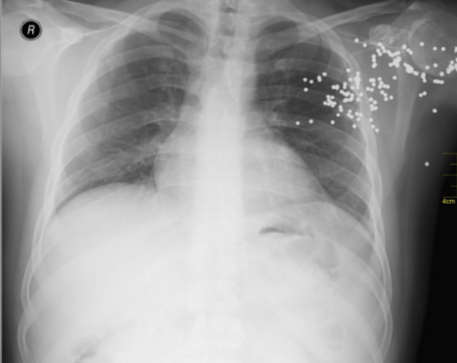

radiography

uses x-rays to visualize internal structures

x-ray

dark = less dense

bright = more dense